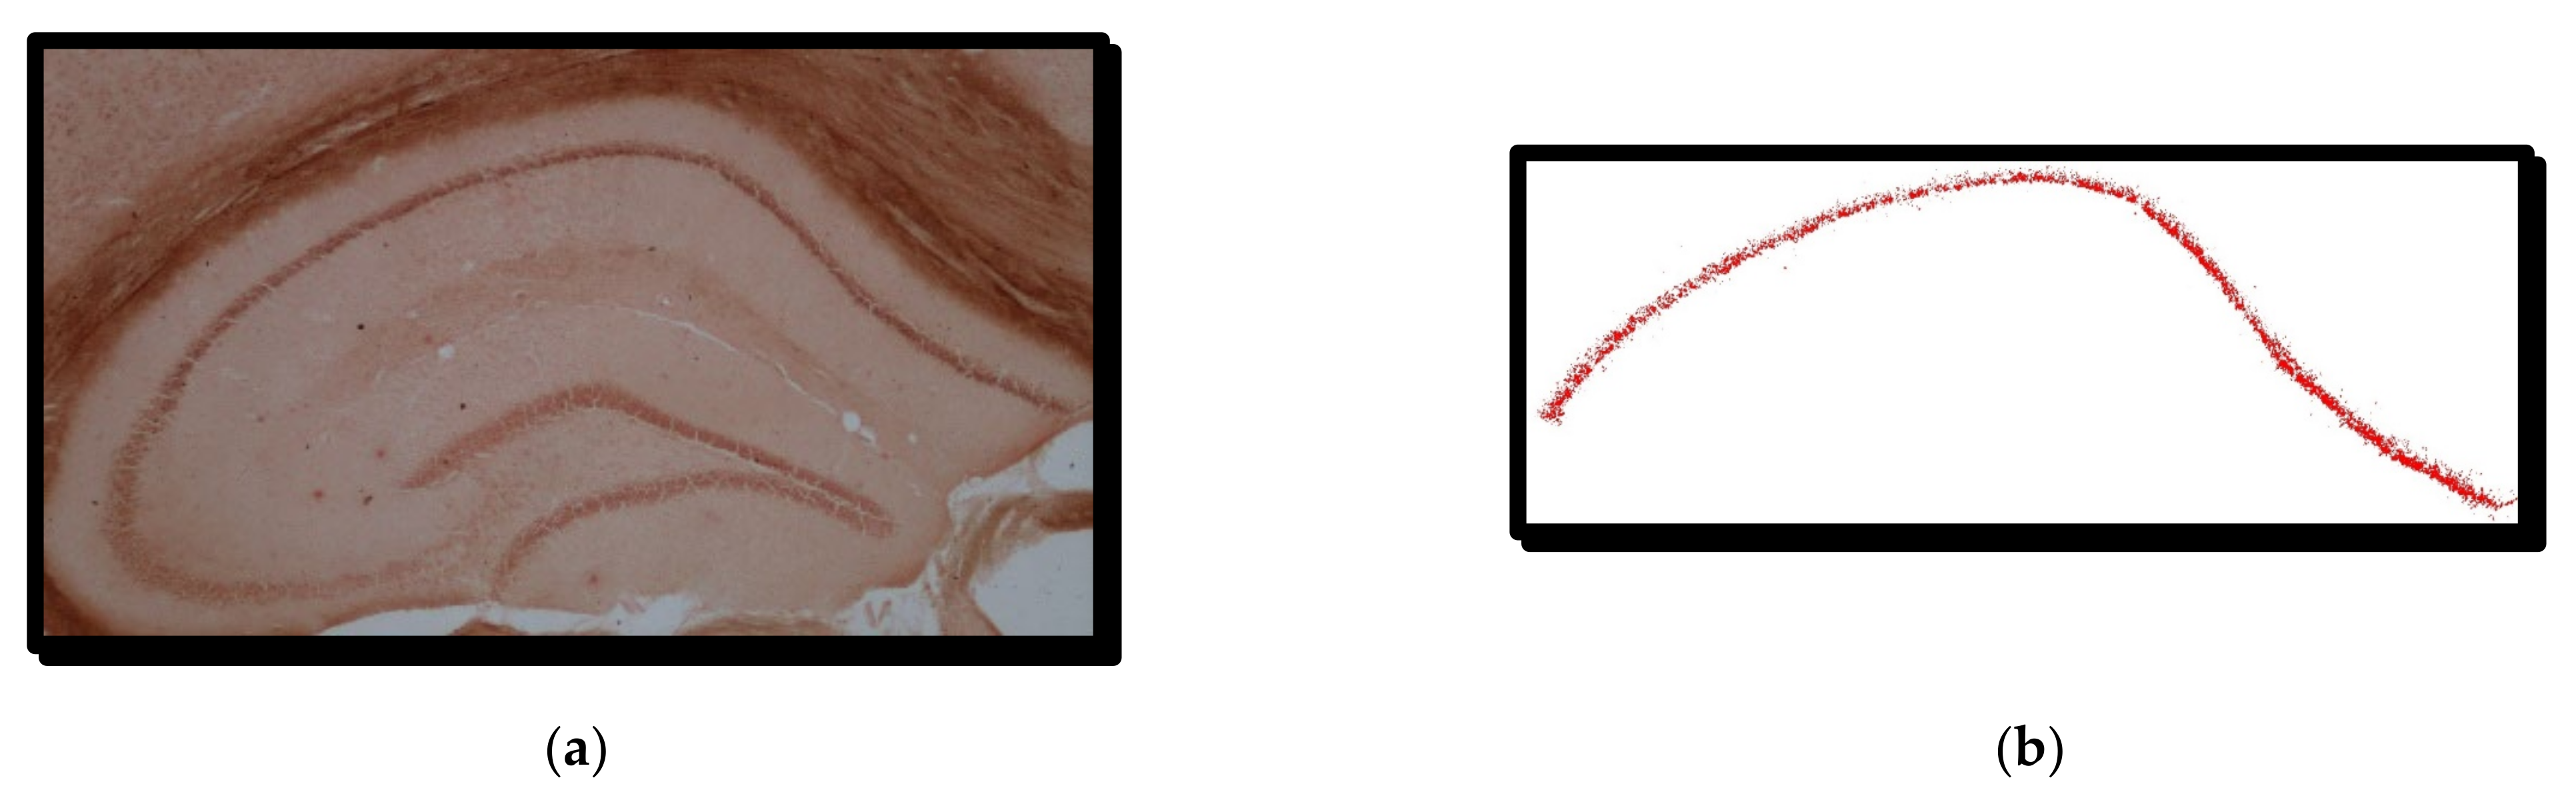

3.1. Animal Brain Samples

3.2. Histological Staining

3.3. Microscopy

4.1. RGB Thresholding Algorithm—The First Method